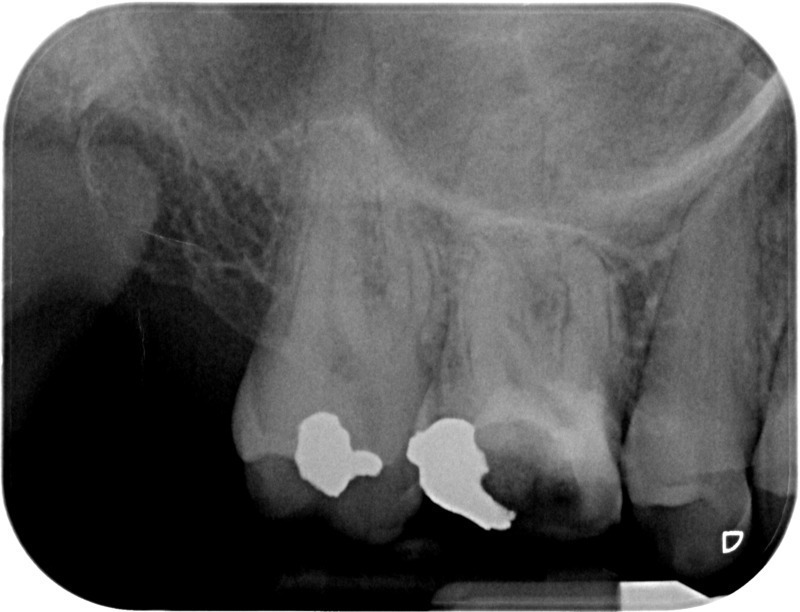

• Traitement endodontique : Sous anesthésie locale et à travers la protection d’un champ opératoire nous accédons à la pulpe de la dent à soigner, puis aux canaux de ses racines que nous devons désinfecter. Ce soin nécessite l’élimination complète de la source de contamination (souvent la carie) parfois sous une ancienne reconstitution ou une couronne qu’il faut alors retirer. Une fois le nettoyage et la mise en forme des canaux réalisés, nous les obturons de façon hermétique avec un ciment et un matériau thermoplastique appelé Gutta Percha. Ceci afin d’empêcher une nouvelle prolifération bactérienne et d’assurer le maintien de la dent dans ses structures de soutien (ligament parodontal et os alvéolaire). L’ouverture effectuée au centre de la dent sera d’abord refermée avec un pansement provisoire avant d’envisager ensemble la reconstitution d’usage : un composite, un inlay-onlay ou une couronne.

Avant

Après